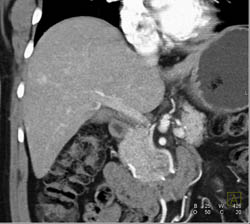

Hepatic Infarcts